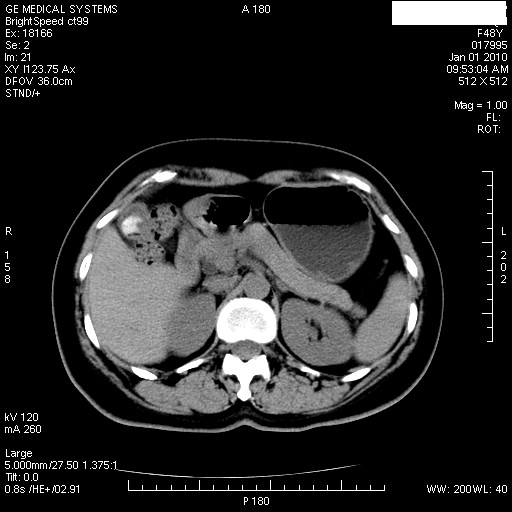

经过抗炎解痉镇痛治疗一周后复查ct如下:

1.图像看上去不是同一人(前组图像十二指肠未见明显异常,后组图像可见十二指肠占位)

2.后组图象印像

a.十二指肠球部前壁占位

b.坏蛆性胆囊炎,胆囊-结肠瘘(瘘口微小且时间较短,结肠内容返流入胆囊,形成胆囊壁钙化,胆囊内钙盐等沉积)

c.胆管炎,肝外胆管轻度扩张

坏蛆性胆囊炎,胆囊-结肠瘘,胆囊内钙盐等沉积.

1)肝内外胆管扩张,原因待查。2)胆囊内药物沉积?